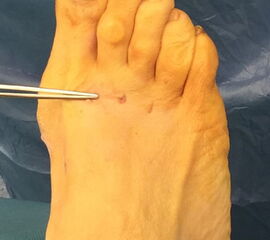

Das hier vorgestellte Konzept beruht auf den grundsätzlichen Überlegungen von Sharma, unter Anwendung der Prinzipien der minimalinvasiven Fußchirurgie. Die Korrektur der Adduktionsfehlstellung der Metatarsalia II bis IV erfolgt über eine modifizierte, lateralisierende, distale, minimalinvasive Metatarsale-Osteotomie (DMMO) (interner Link: OP Technik DMMO). Die Osteotomie der Metatarsalia II bis IV ohne Osteosynthese erlaubt eine limitierte Verlagerung der Metatarsaleköpfchen nach kranial, was ein etabliertes Verfahren zur Therapie einer Metatarsalgie darstellt 7. Eine zusätzliche, im Normalfall unerwünschte Lateralverschiebung der Metatarsaleköpfchen kann bei einem Pes adductus zur Korrektur genutzt werden. Verglichen zu offenen Therapieverfahren ermöglicht dieses Konzept die Korrektur der Adduktionsstellung der Metatarsalia II bis IV bei minimiertem Weichteiltrauma und verkürzter die OP-Dauer. Persönliche Erfahrungen mit dem Verfahren deuten darüber hinaus auf ein geringeres postoperatives Schmerzniveau, eine einfachere Mobilisierbarkeit und eine hohe kosmetische Zufriedenheit hin.

• Fuß ist auf der unteren Tischkante gelagert, so dass der Zugang von allen Seiten möglich ist (Abb. 3).

Zum Lesen der Bildbeschreibung und zur Vollansicht bitte die Bilder anklicken.